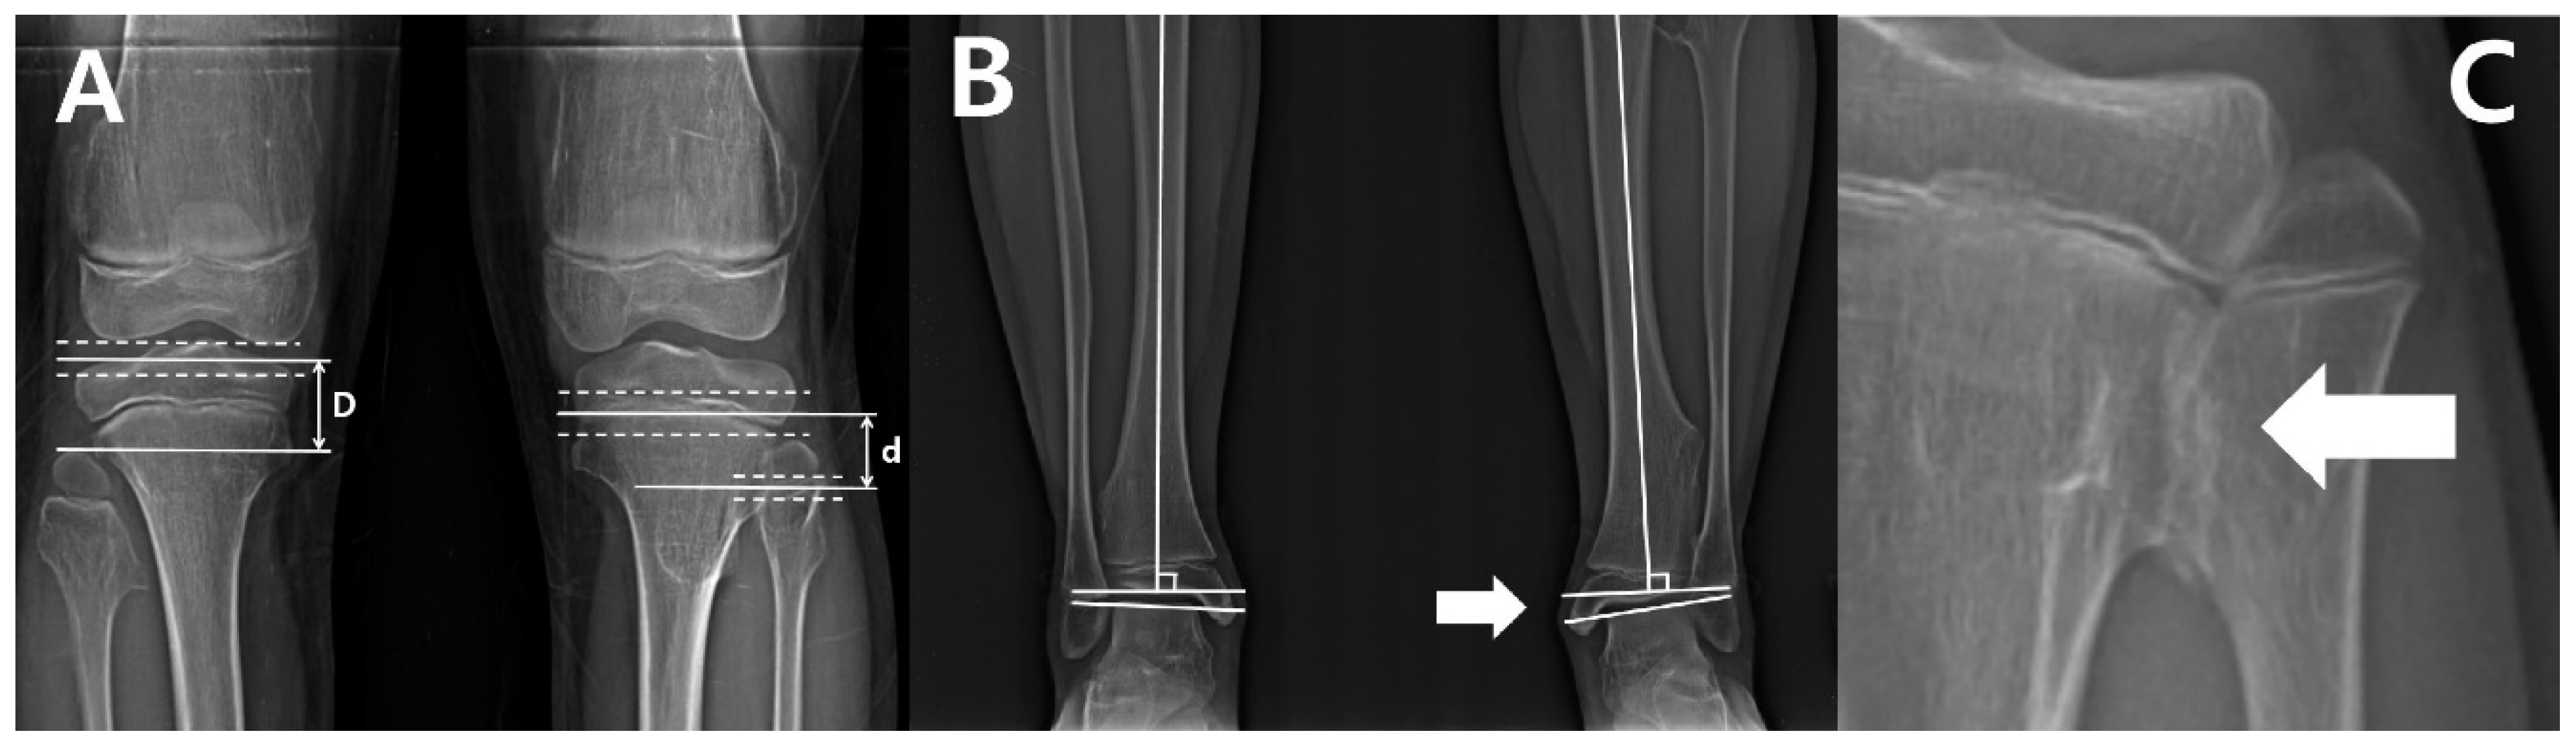

Anatomical LDFA was defined as the lateral angle between the longitudinal axis of the femoral shaft and a line across the surface of the distal femoral epiphysis. Mechanical MPTA was defined as the medial angle between the longitudinal axis of the tibial shaft and a line across the tibial plateaus. The fibular length was measured as the straight-line distance from the tip of the proximal epiphysis to the tip of the lateral malleolus; the tibial length was measured as the straight-line distance from the tips of the tibial eminences to the tibial plafond. We also measured the distance between the tips of the tibial and fibular epiphyses, respectively. Proximally, due to the complex anatomy of the proximal tibial epiphysis, the distance was defined as the gap between a parallel line past the apex of the proximal fibula and a parallel line through the midpoint between the line along the apex of the tibial spine and a line on the bottom-most portion of the condyle. Additionally, a parallel line through the midpoints between a line passing the top of the physis and a line crossing the bottom of physis were set as a reference line in order to measure the distance between the proximal and distal fibular and tibial physes (Figure 1A). The tibiotalar angle was defined as the medial angle between a perpendicular line to the axis of the tibia and the extended line that touches the articular surface of the talus (Figure 1B) [6]. In order to categorize the initial ankle alignment, the cases were divided into three positions: neutral (tibiotalar angle = 0–5°), valgus (tibiotalar angle > 5°), and varus (tibiotalar angle < 0°) [13].

The presence of tibiofibular synostosis was determined when definite bridging by an exostosis lesion of the tibia and fibula, without overlapping cortices, was identified (Figure 1C). The location of osteochondromas were determined by dividing the entire length of the fibula and tibia, including both ends of the proximal and distal epiphysis, into two equal parts [10].

Figure 1. (A) The distance of proximal epiphyses (D) and physes (d) between tibia and fibula. The distance of proximal epiphyses was defined as the gap between the parallel line past the apex of the proximal fibula and the parallel line past the center of the distance between the line across the apex of the tibial spine and the most bottom of the condyle. The distances of proximal physes was defined as the gap between the parallel line passing through the midpoint of the distance between the line across the top of physis; the line crossing the bottom of physis was set as the reference line. (B) The measurement of the ankle joint. The tibiotalar angle was defined as the extension line of the tibial anatomical axis and a line perpendicular to the extension line that touches the dome of the talus. The left lower extremity indicated by the white arrow demonstrates a decreased distal tibiofibular distance compared to the right side, and a prominent ankle valgus deformity is also observed. (C) The tibiofibular synostosis. The white arrow indicates a definite bridge of an exostosis lesion connecting the proximal fibula and tibia without the overlapping cortex.